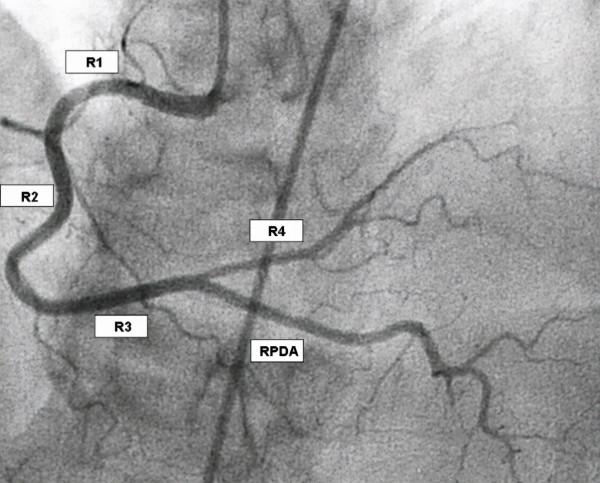

如果你聽說過冠心病,那麼你一定對這種疾病有所瞭解,其實這是一個簡稱,如果把他的全稱說出來,你可能就有一些陌生了:

冠狀動脈粥樣硬化性心臟病。

指的是冠狀動脈發生的粥樣硬化,所以管腔狹窄或者閉塞,於是心臟的肌肉細胞就容易缺血、缺氧,出現壞死。

在一些嚴重的患者當中,醫生往往建議應用心臟支架來進行治療,把閉塞的血管開啟。